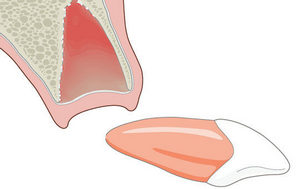

В некоторых случаях можно сделать реплантацию зуба

Старая забытая классика «реплантация зубов» сейчас снова набирает популярность в разрезе применения современных технологий. Это достаточно эффективный и менее дорогой способ восстановления зубного ряда по сравнению с имплантацией. Сутью методики является возвращение подлежащего удалению зуба на свое место в качестве натурального импланта. Характерная особенность двухчасовой операции — кропотливая работа врача, а также сохранение целостности соседних зубов.

Процедура выполняется в несколько этапов:

- удаление зуба;

- очищение лунки;

- противовоспалительная терапия;

- пломбировка каналов, дырок, полировка;

- возвращение на прежнее место с закладкой под имплант специального лекарства;

- фиксация при помощи фотополимерной нити к соседним единицам.

Спустя некоторое время после операции происходит рассасывание лекарства, что способствует восстановлению кости, а также надежному закреплению реимплантата. Приживление, как правило, занимает три месяца (в обычной имплантации — до 9 месяцев).

Преимущества методики:

- нет необходимости обточки близлежащих зубов;

- минимальный риск отторжения;

- относительно невысокая стоимость по соотношению к обычной имплантации.

Положительный момент — человек получает зуб незамедлительно. В то время как, традиционная имплантология подразумевает постановку коронки только через 6 месяцев.